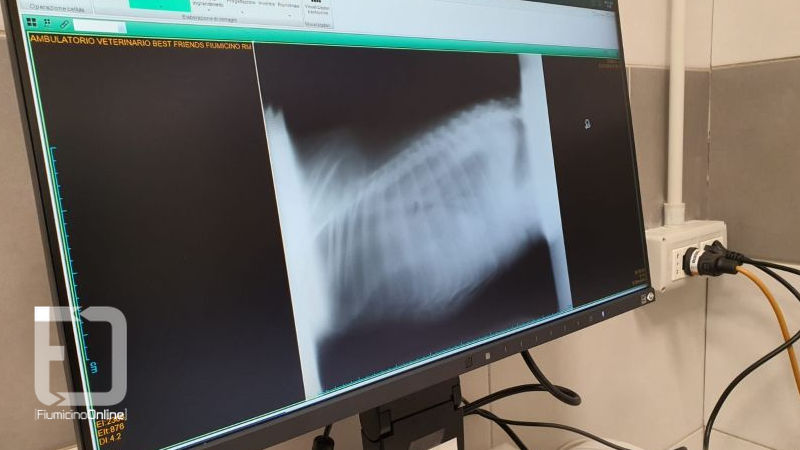

Un apparecchio molto importante utilizzato per lo studio radiografico di tutti i distretti corporei (torace, addome, cranio, colonna vertebrale, arti) a fini diagnostici, prognostici e terapeutici.

“Un apparecchio radiologico ad alta frequenza con una tecnologia di ultima generazione – spiega il dottor Alessandro Marcenta – paragonabile a quella utilizzata negli ospedali per gli umani. Utilizzando questo innovativo apparecchio, è possibile approfondire in dettaglio lo stato delle ossa e degli organi interni, con una grande variabilità di funzioni. Gli organi cavi e ripieni di aria, come l’intestino lo stomaco ed i polmoni, possono essere sottoposti ad un’indagine molto più approfondita. Inoltre è possibile individuare la presenza di corpi estranei e valutare meglio lo stato di salute del cuore”.